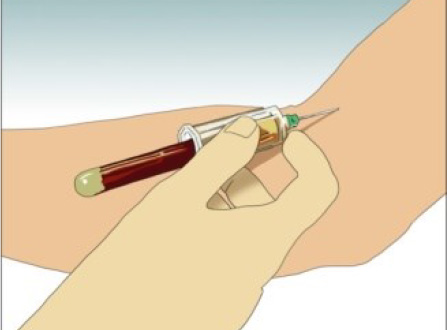

Tuberculosis (TB) remains a major preventable cause of morbidity. Bacillus Calmette Guerin (BCG) vaccines are widely used to protect against TB. Their efficacy shortly after vaccination has been demonProject - "If you have a positive IGRA test" in many languages

"If you have a positive IGRA test" in many languages

Last update

Each information note explains what it means to test positive, if it is dangerous or not, if the patient is infectious and what to be aware of.Information note